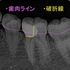

レントゲン

2026 EEdental NAM (1).jpg

近心根が折れているような所見があり、根尖にはファイル(金属ヤスリ)破折が2本見られます。

患者さんには、折れており保存治療は難しいこと

保存を行おうとすれば、「接着修復」←私はやっていない(正確に言うと才能なく辞めた)

私が出来るのはヘミセクション(分割抜歯)ぐらい・・・

患者さんにOKをもらい

2026 EEdental NAM (2).jpg

まずは根管治療を行い

折れた歯の分割抜歯

一般的にはブリッジにするケースですが、個人的には1本で支え使える所まで使ってもらいます。

2026 EEdental NAM (3).jpg